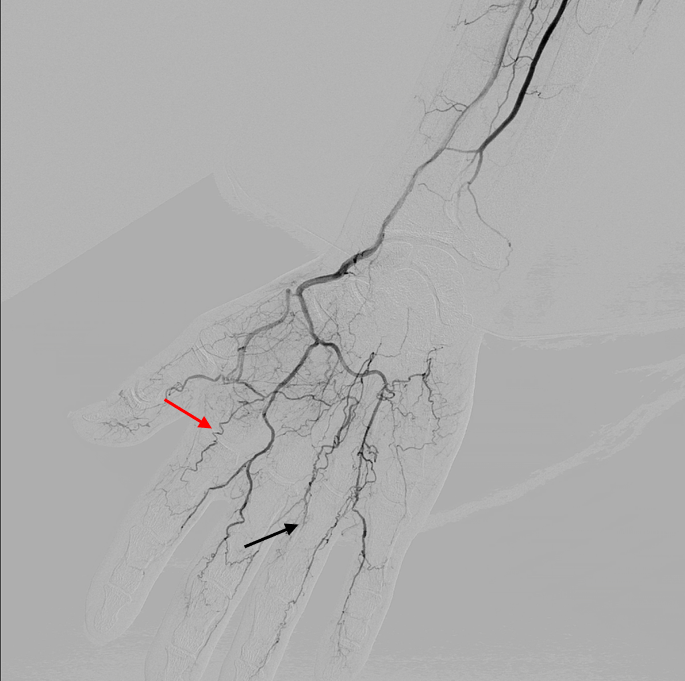

Corkscrew Collaterals in Thromboangitis Obliterans (Buerger’s Disease Buerger's Disease (Thromboangiitis Obliterans) Buerger’s disease (thromboangiitis obliterans) is a rare disease of the blood vessels in your arms, legs, fingers and toes. Thromboangiitis obliterans (tao), also called buerger disease, is a nonatherosclerotic, segmental, inflammatory. Buerger disease, also known as thromboangiitis obliterans (tao) is a progressive, nonatherosclerotic, segmental, inflammatory disease that most often affects small and. Highest incidence is in young men of southeast.. Buerger's Disease (Thromboangiitis Obliterans).